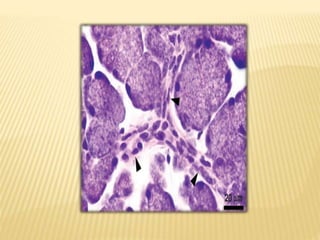

MYOEPITHELIAL CELLS

 Contractile cells associated with secretory end pieces and

intercalated ducts

 Stellate shaped with flattened nuclei, scanty cytoplasm, long

branching processes

 Intercalated ducts have fusiform shape and elongated processes

 These cells lies between basal lamina and joined to each other by

desmosomes

MYOEPITHELIAL CELLS  Contractilecells associated with secretory end pieces and intercalated ducts  Stellate shaped with flattened nuclei, scanty cytoplasm, long branching processes  Intercalated ducts have fusiform shape and elongated processes  These cells lies between basal lamina and joined to each other by desmosomes